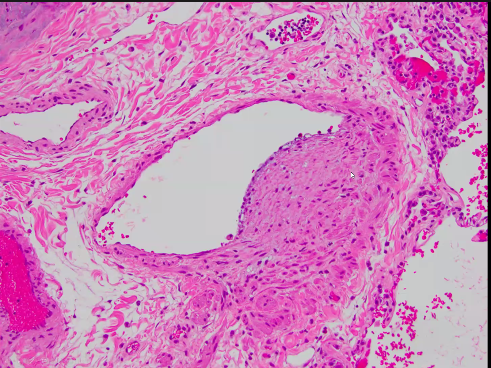

This of course means we now have pathology...Dr. Zetlen (with appreciation to our pathologist extraordinaire Dr. Lida Hariri) shows smooth muscle hypertrophy of pulmonary veins/venules, some completely occluded.

The arteries did not get away either.